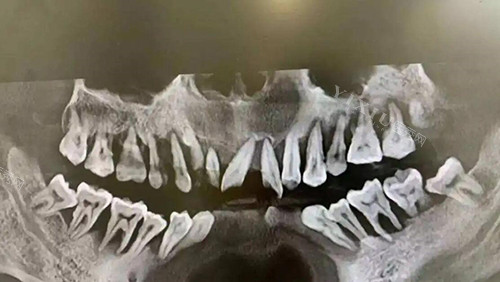

牙槽骨吸收是牙周疾病常见的病理改变,根据吸收方向可分为水平吸收和垂直吸收两种类型。这两种吸收形式的治疗方式既有相似之处,也存在一些差异。

牙槽骨缺失照片图